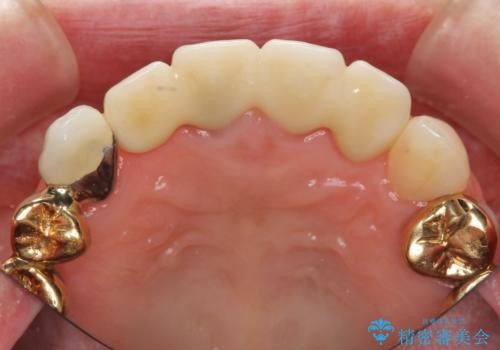

視診・X線写真検査より根尖性歯周炎が認められ再治療が必要な状態です。

再根管治療を行うべくクラウン除去を行ったところ、右上側切歯に保存不可能な垂直性の破折が認められたため抜去が必要になりました。

即切歯の抜歯を行う場合犬歯を含めたブリッジによる補綴計画を立てることが多いですが、今回は犬歯から大臼歯にかかる大きなブリッジが既に装着されていたため予算とご希望を相談し前歯のみの延長ブリッジ補綴で治療を行っていくこととしました。

- 54万円(仮歯・感染根管治療・ファイバーコア・ジルコニアクラウン×4) (税別)費用は治療当時の料金となります